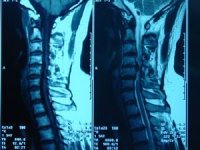

2CT的MRI检查:重症患者或不典型的病例在诊断有困难时,可考虑作脊髓碘油造影CT扫描和磁共振等特殊检查以明确诊断及突出部位